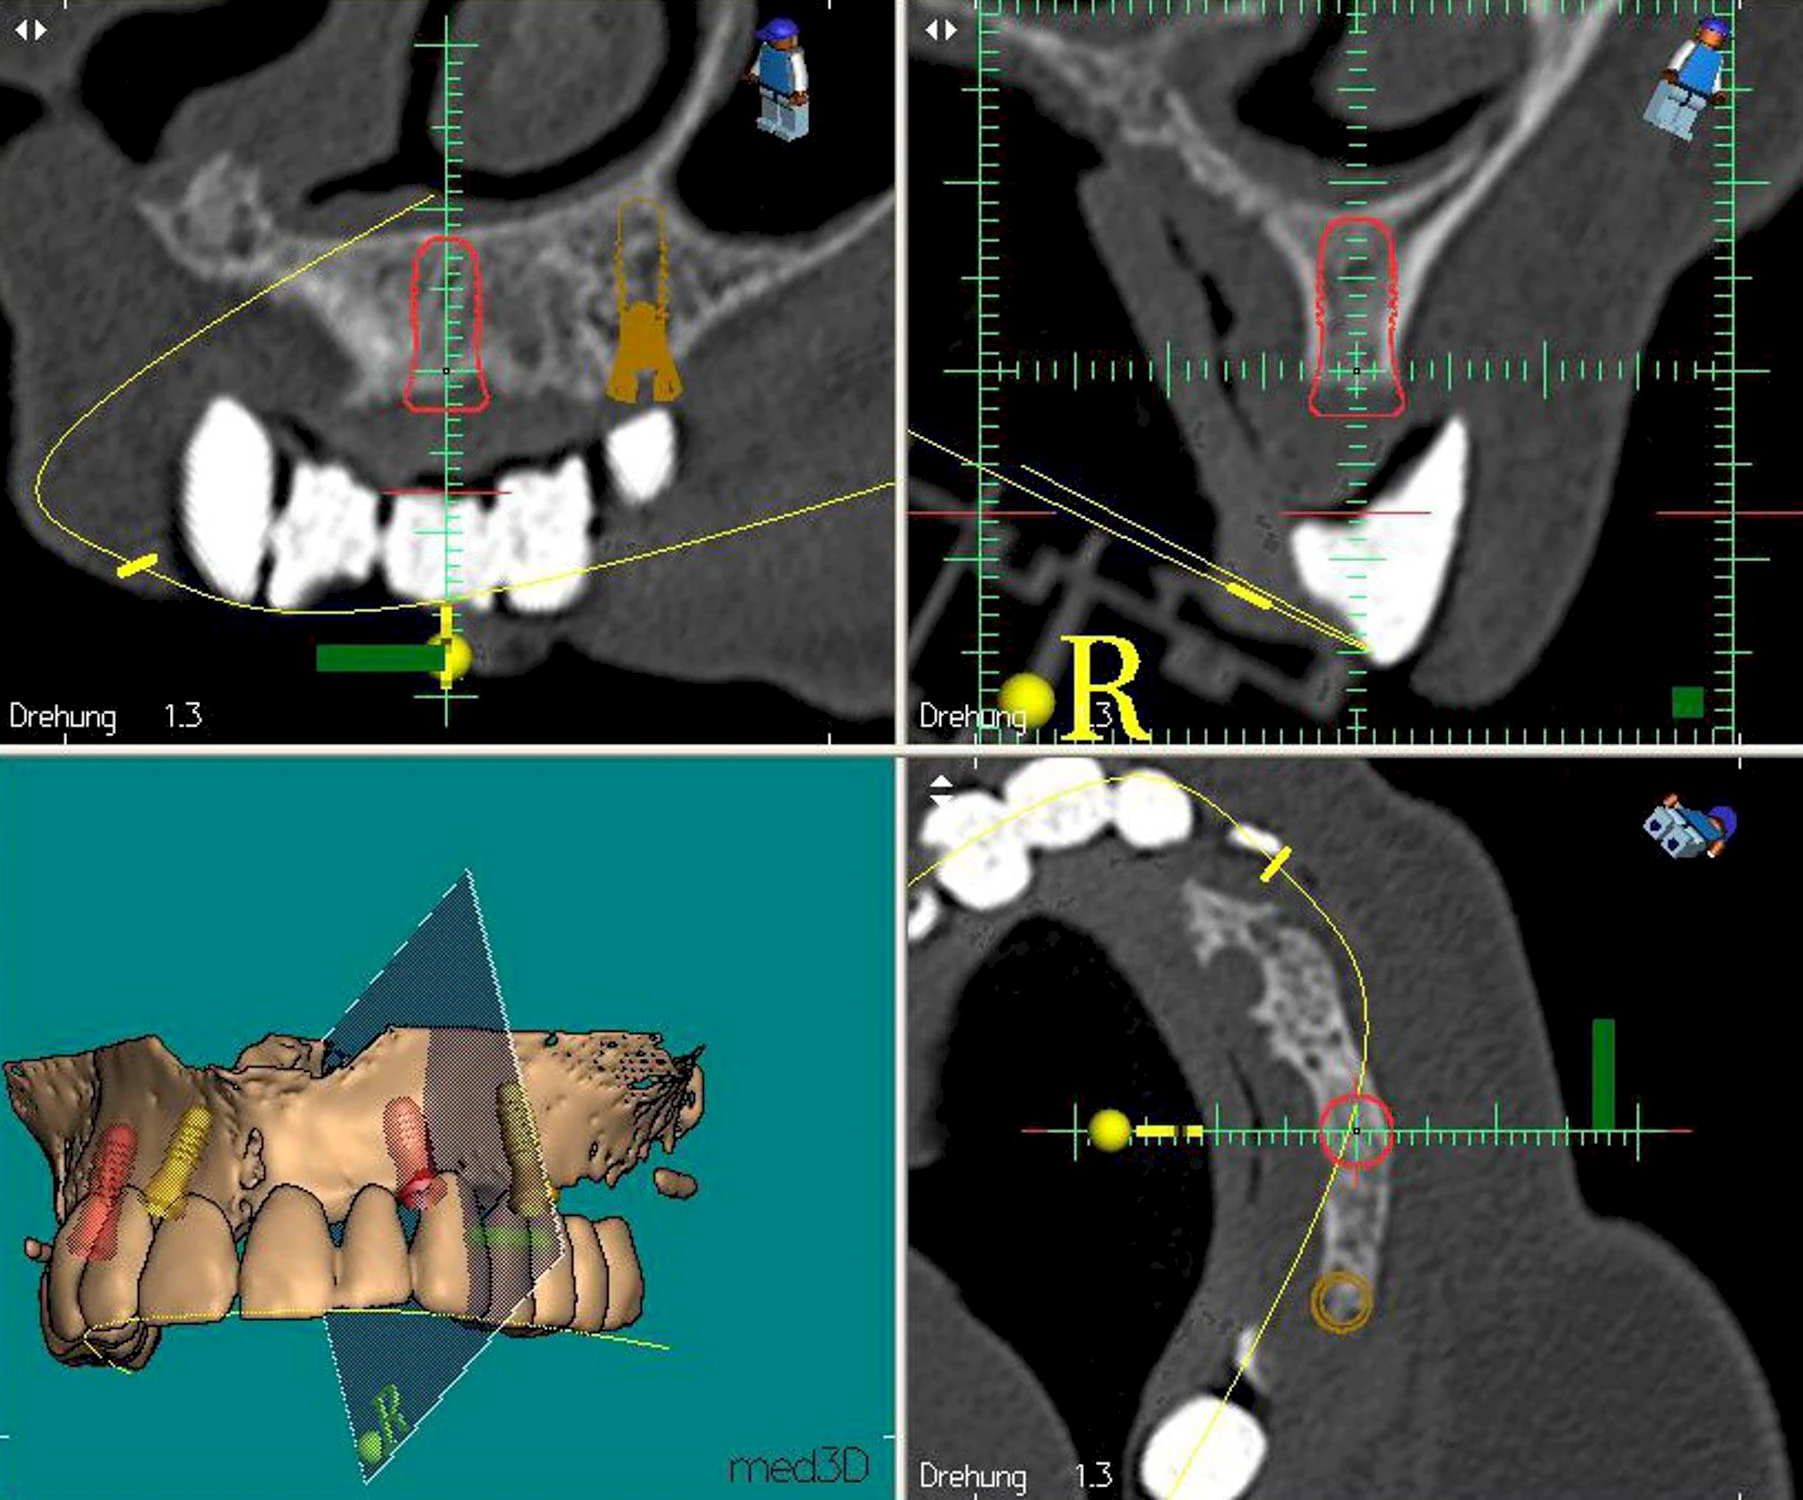

Damit Implantate an der richtigen Stelle im Kieferknochen platziert werden könen, gibt es heute vielfältige Möglichkeiten der Planung. In vielen Situationen kann die Erfahrung des Zahnarztes ausreichend sein.

Nicht selten ist jedoch auch eine technisch aufwändigere Vermessung im Vorfeld sinnvoll, z. B.:

- Wenn sich der Kieferknochen abgebaut hat

- Wenn der Nervverlauf im Unterkiefer beachtet werden muss

- Wenn die Ausdehung der Kieferhöhle im Oberkiefer beachtet werden muss

- Wenn wenige Restzähne keine gute Orientierung erlauben

In diesen Fällen kann die Planung mittels verschieden aufwendiger Röntgen-Techniken (Übersichtsaufnahme, DVT) ggf. unter Zuhilfenahme speziell angefertigter Planungsschablonen sinnvoll sein.